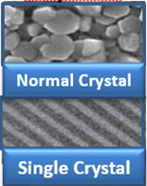

Single crystal transducers with 3T technology:

It’s based on single crystal with Mindray unique 3T tehnology (Triple-matching layers, Total-cut design, Thermal control), providing a wider bandwidth to simultaneously offer better penetration and higher resolution, resulting in an optimum scanning solution for technically difficult patients.